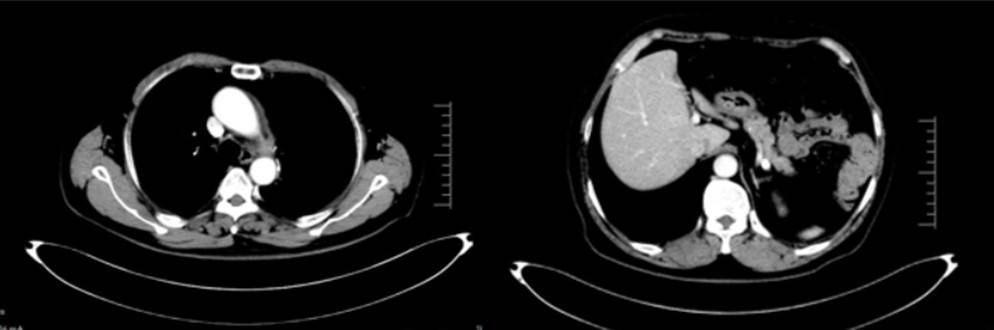

2024年3月4日(5月后):左侧锁骨上区、纵隔及左肺门区多发小淋巴结大致同前,肝S4转移瘤显示不清;

2024年9月19日(11月后):左侧锁骨上区、纵隔及左肺门区多发小淋巴结大致同前,左残肺及右肺小结节灶较前变化不明显;